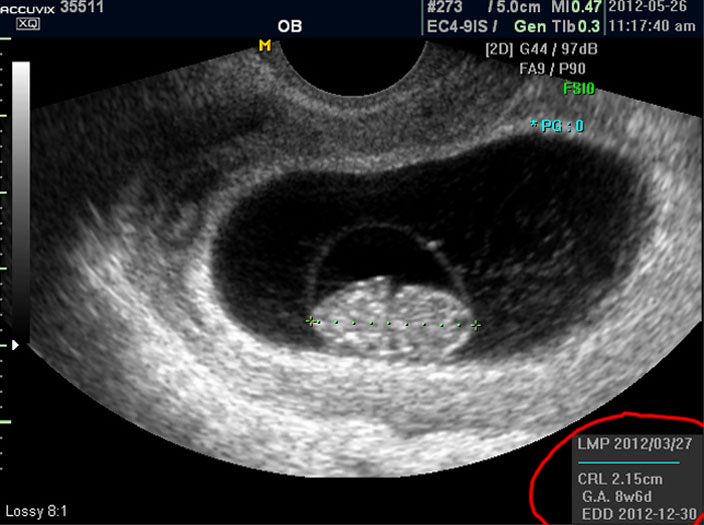

마지막으로 볼 것은 아기의 정보를 나타내 주는 수치들입니다.

으로 우측의 LMP라고 된 숫자는 산모의 최종 월경일이며 이는 초음파로 판단한 것이 아니라 산모의 진술을 바탕으로 한 것인데 이것이 중요한 이유는 초음파는 그저 크기만을 알아 내는 것이라 임신 주수에 걸맞게 잘 자라는지 판단하려면 월경 주기를 알아야 하기 때문입니다.

그 아래 보이는 CRL이라는 것은 Crown Rump Length의 약자로 아기의 머리부터 엉덩이 끝까지의 실제 길이입니다.

임신 12주 내지 13주 정도의 초반기의 아기 발육은 주로 아기의 전체 크기를 가지고 판단하는데 엉덩이까지 체크하는 이유는 흔히 태아는 다리를 구부리고 있기 때문에 성인 인간처럼 머리끝부터 발끝까지 실제 키를 재기가 어렵기 때문입니다.

그 아래 GA 는 Gestational Age의 약자로 우리말로는 태령이라고 하며 초음파의 CRL을 기준으로 했을 때 어느 시기의 태아의 수준인가를 말해 주는 것입니다.

따라서 산모의 LMP를 기준으로 한 태령과 초음파로 측정한 태아의 태령은 1주 정도의 오차로 비슷한 것이 정상이며 간혹 최종 월경일을 틀리게 알고 있거나 아기의 발육에 문제가 있을 때는 큰 차이가 날 수 있습니다.

맨 아래의 EDD는 Estimated Due Date의 약자로 출산 예정일을 말하는데 초음파를 기준으로 했을 때 이정도 시기가 출산 예정일이 될 것이라는 계산입니다.

그러나 이것은 어디까지나 초음파로 예상한 시기이며 실제 출산은 앞뒤로 2주 씩의 오차가 있을 수 있습니다.